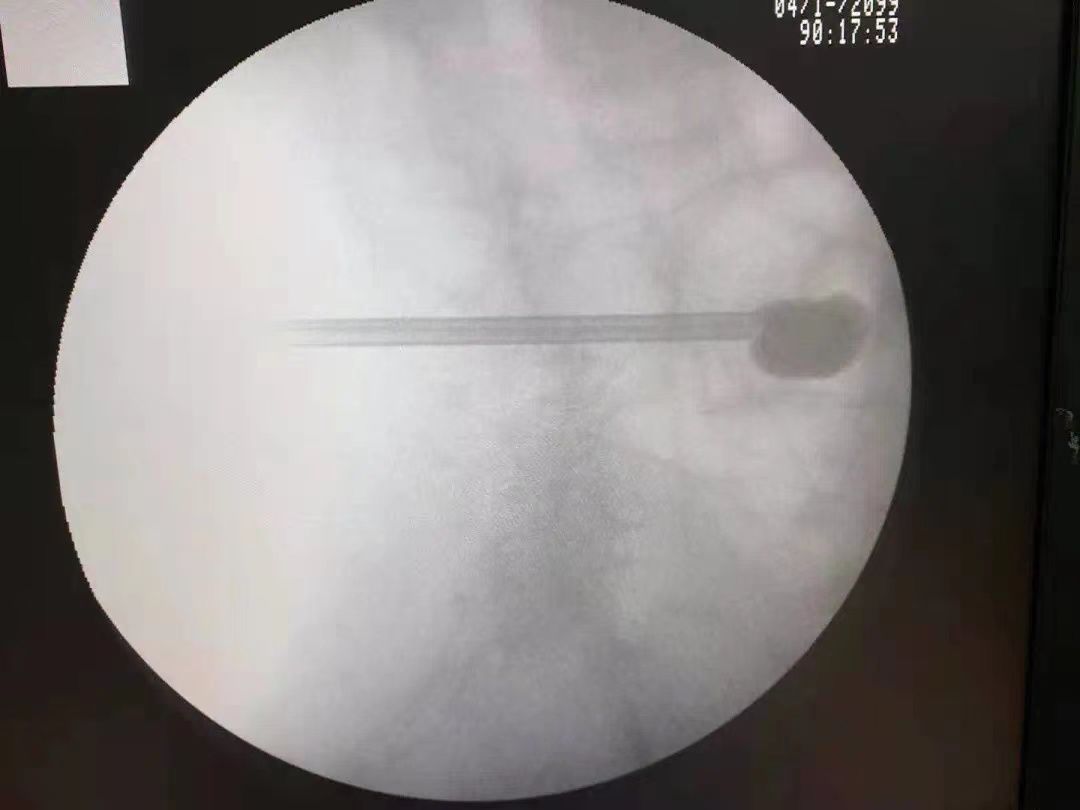

走在四川省甘孜州稻城县的街头,余杭区第二人民医院骨科副主任中医师张浩经常被当地百姓认出来。就在不久前,他成功实施了当地首例脊柱微创手术,这也是当地首例椎体成形术。

“高龄患者做手术确实存在一定风险,但是不做手术,选择保守治疗的话,需要长期卧床,可能会引起褥疮、肺部感染等并发症,对原本体质就弱的普珍奶奶来说无疑是雪上加霜。”针对患者的情况,张浩提出了选择——经皮球囊扩张椎体后凸成形术。

这是一种微创技术,只需在局部麻醉下,通过“一根针”将可膨胀性球囊置入椎体内,球囊膨胀扩张使骨折椎体复位,在骨折椎体内打造出一个安全有效的空间,然后灌注骨水泥,稳定病变椎体,从而减轻骨折带来的疼痛。“这种手术创伤小,时间短,术后恢复也快。”张浩的负责最终取得了患者和家属的信任。